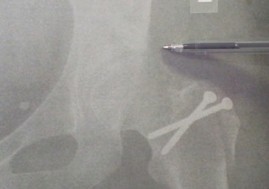

- Plain Radiographs: AP pelvis, lateral Dunn view (45° flexion, 20° abduction), false profile view, and cross-table lateral are crucial to assess femoral and acetabular morphology. Identify alpha angle, lateral center-edge angle, Tönnis angle, presence of crossover sign, posterior wall sign, and ischial spine sign.

- CT with 3D Reconstruction: Considered the gold standard for defining complex osseous deformities, particularly for planning precise osteotomies of the femoral head-neck junction and acetabular rim. Critical for assessing femoral version and acetabular version. Templating of osteotomies can be performed using 3D models.

- Surgical Templating: Based on 3D CT reconstructions, surgeons can precisely plan the amount of femoral head-neck osteochondroplasty and acetabular rim trimming required to restore normal morphology and achieve impingement-free range of motion. This also helps anticipate the size and location of fixation for the trochanteric osteotomy.